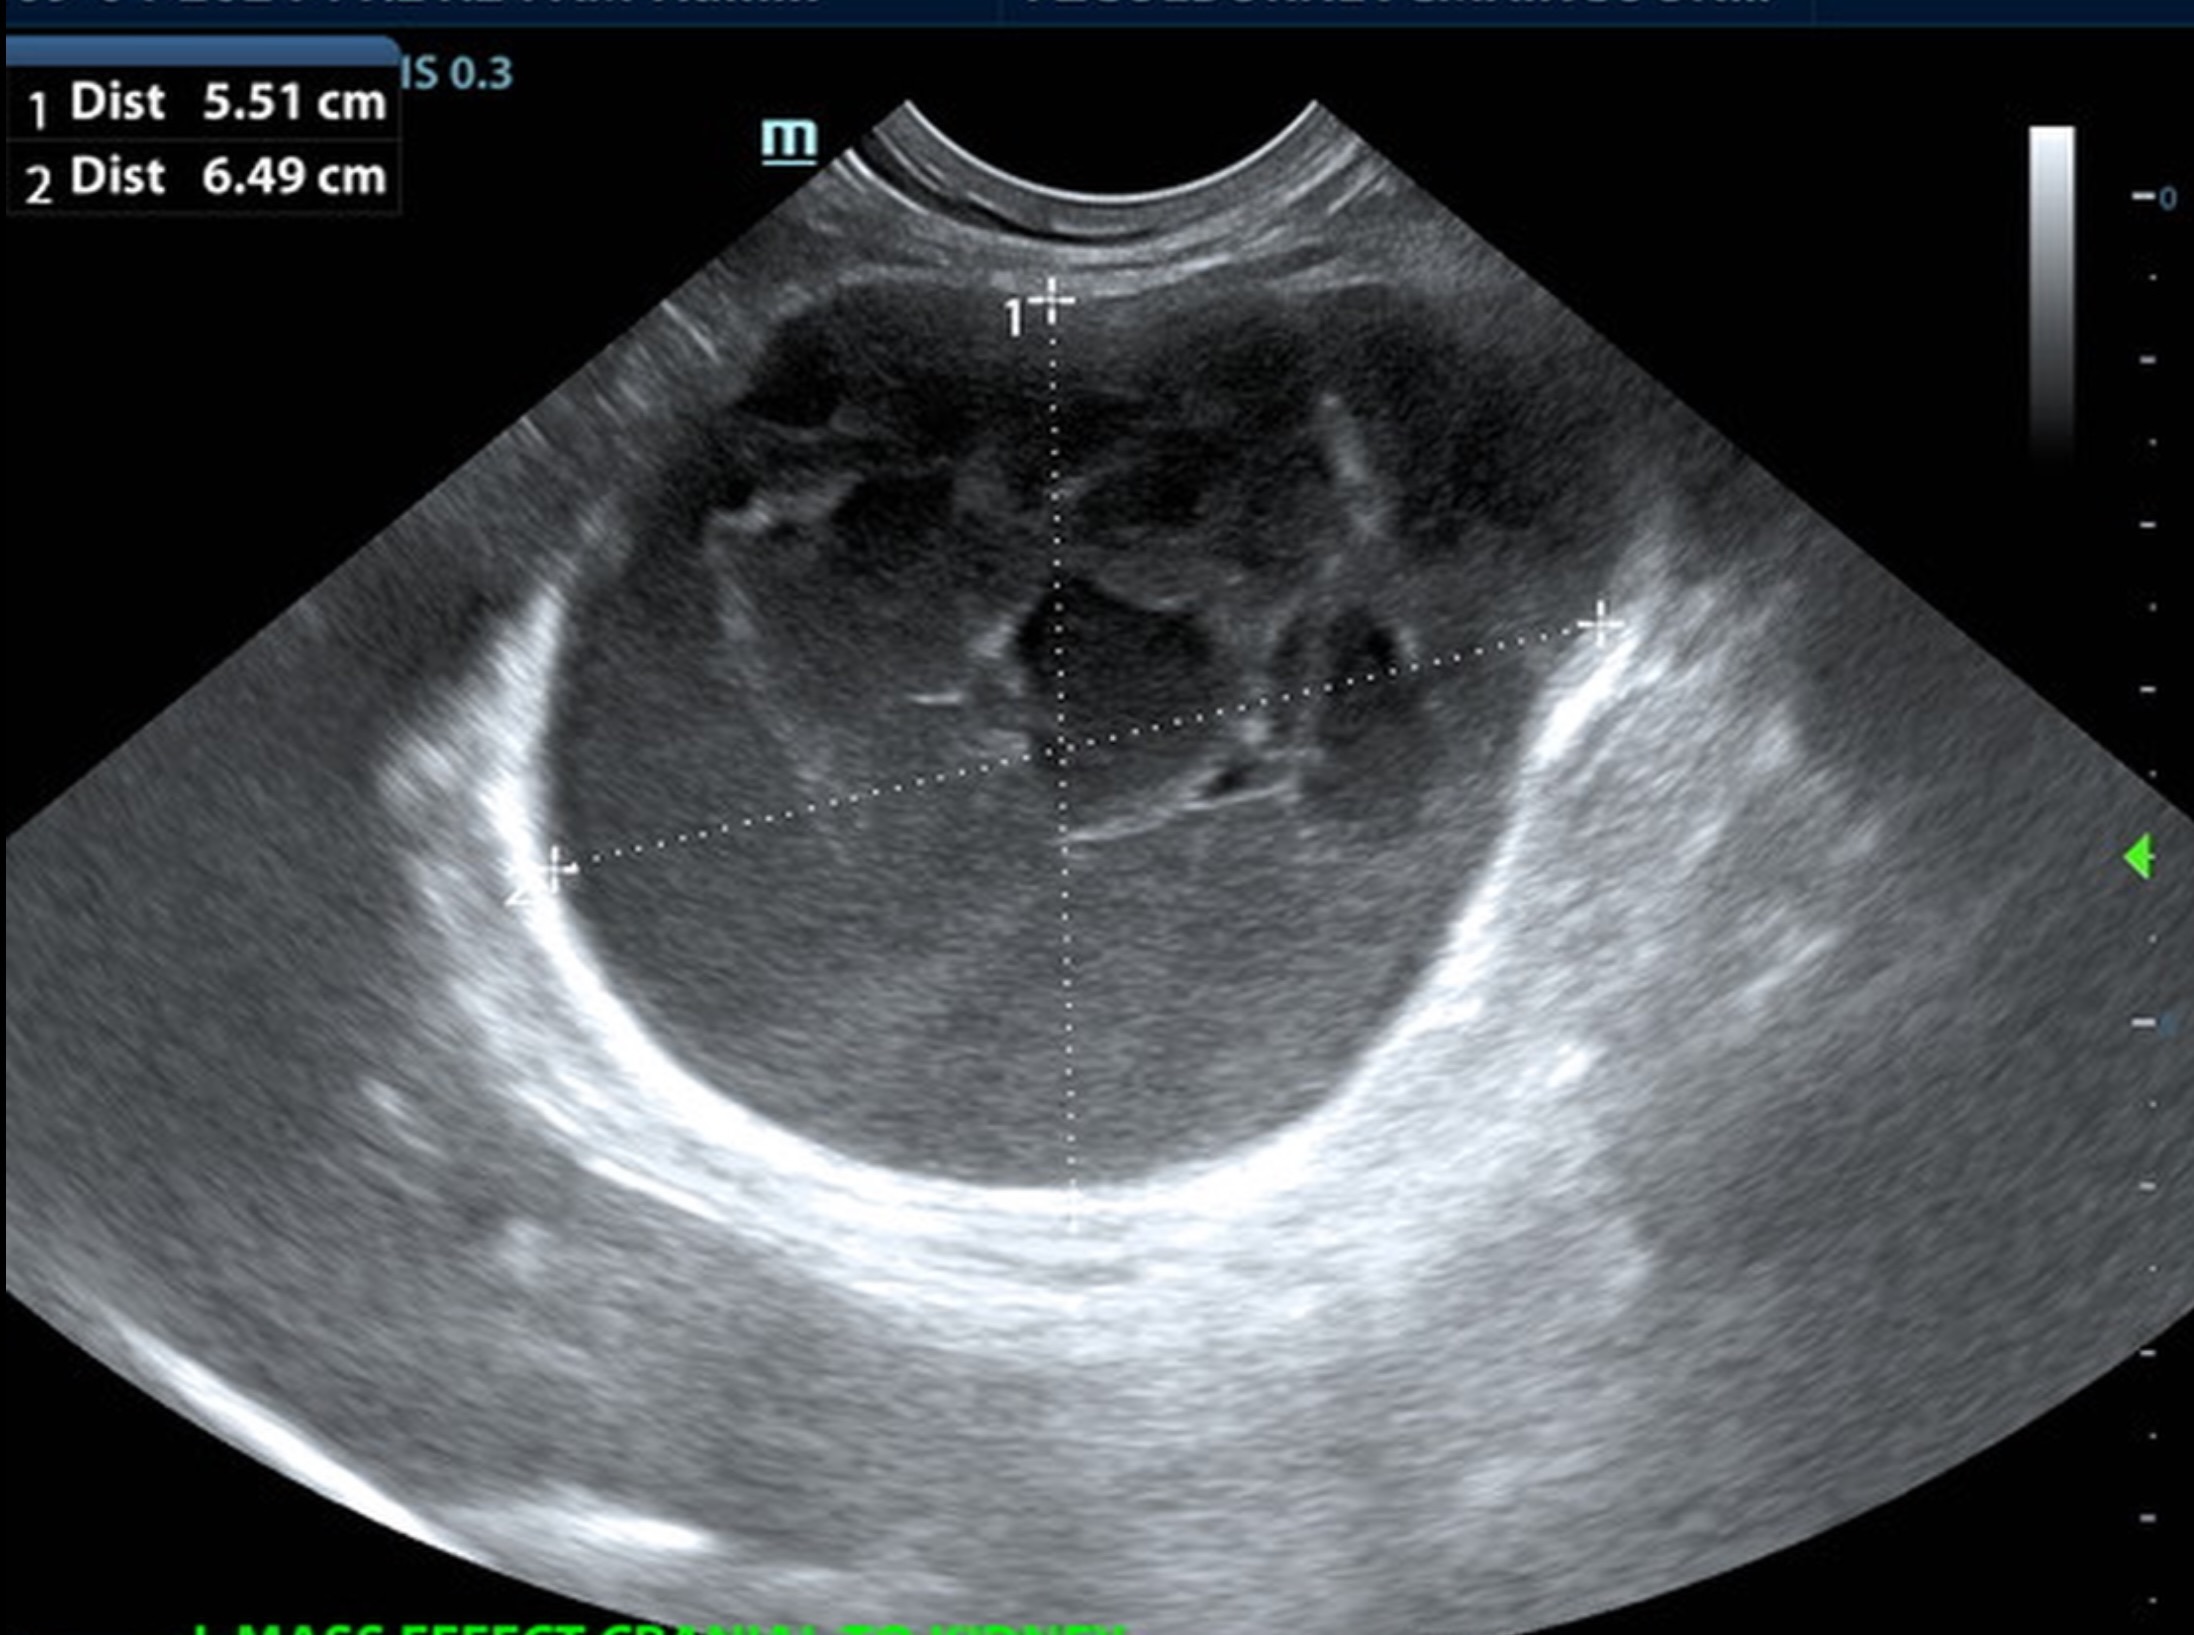

A 6.5 cm hypoechoic abscess was noted in the region of the left pancreatic limb with hyperechoic granulation bed and regional inflammation. The abscess was largely non-vascular. One minor portion of color flow uptake noted within the abscess.

• Large left-sided pancreatic abscess.

Rapid surgical intervention recommended. Ultrasound guided drainage could be considered. However, there is significant potential for leakage, given the turgid pattern of the abscessation. The remainder of the abdomen was unremarkable other than age related changes. Culture and sensitivity indicated. No evidence nor suspicion of neoplasia.